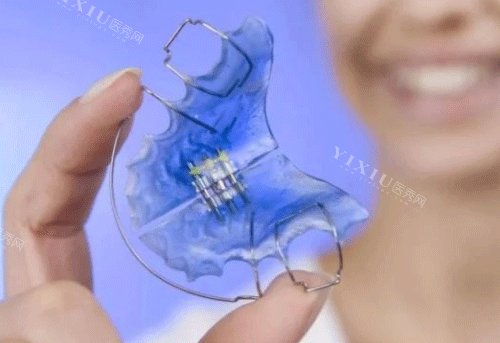

活动扩弓器:价格2000-4800元起,适合儿童。可自行摘戴,但需定期调整,适合慢性扩弓。若孩子配合度高,且牙弓狭窄不重度,活动扩弓器性价比高。

固定扩弓器:价格3000-5000元起,如W簧、Hyrax等,适合需要快速扩弓的病例,尤其是牙弓狭窄的青少年或成人。固定扩弓器稳定性强,但需医生操作,适合复杂病例。

隐形扩弓器:价格5000元起,美观舒适,但技术要求高,价格偏贵。若孩子对美观要求高,且经济允许,隐形扩弓器是不错的选择。